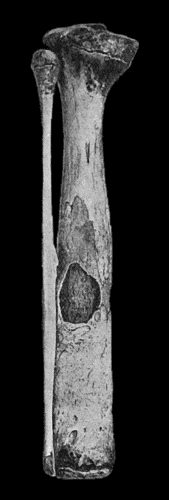

119.Femur and Tibia showing results of Acute Osteomyelitis 445

120.Segment of Tibia resected for Brodie's Abscess 449